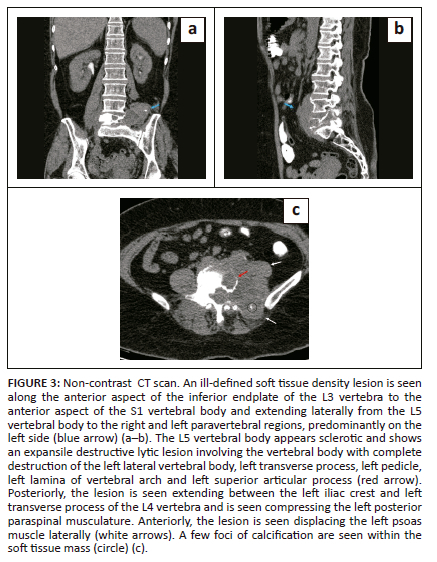

Lumbar spine CT was also performed in April 2023 using the Philips ingenuity core 128-slice multidetector computed tomography (MDCT) scanner. The study revealed an expansile, lytic lesion in the L5 vertebral body with complete destruction of the left transverse process, left pedicle, left lamina and left superior articular process (Figure 3). Tiny lytic areas were also seen involving the right pedicle, right transverse process, right lamina and right superior articular process.